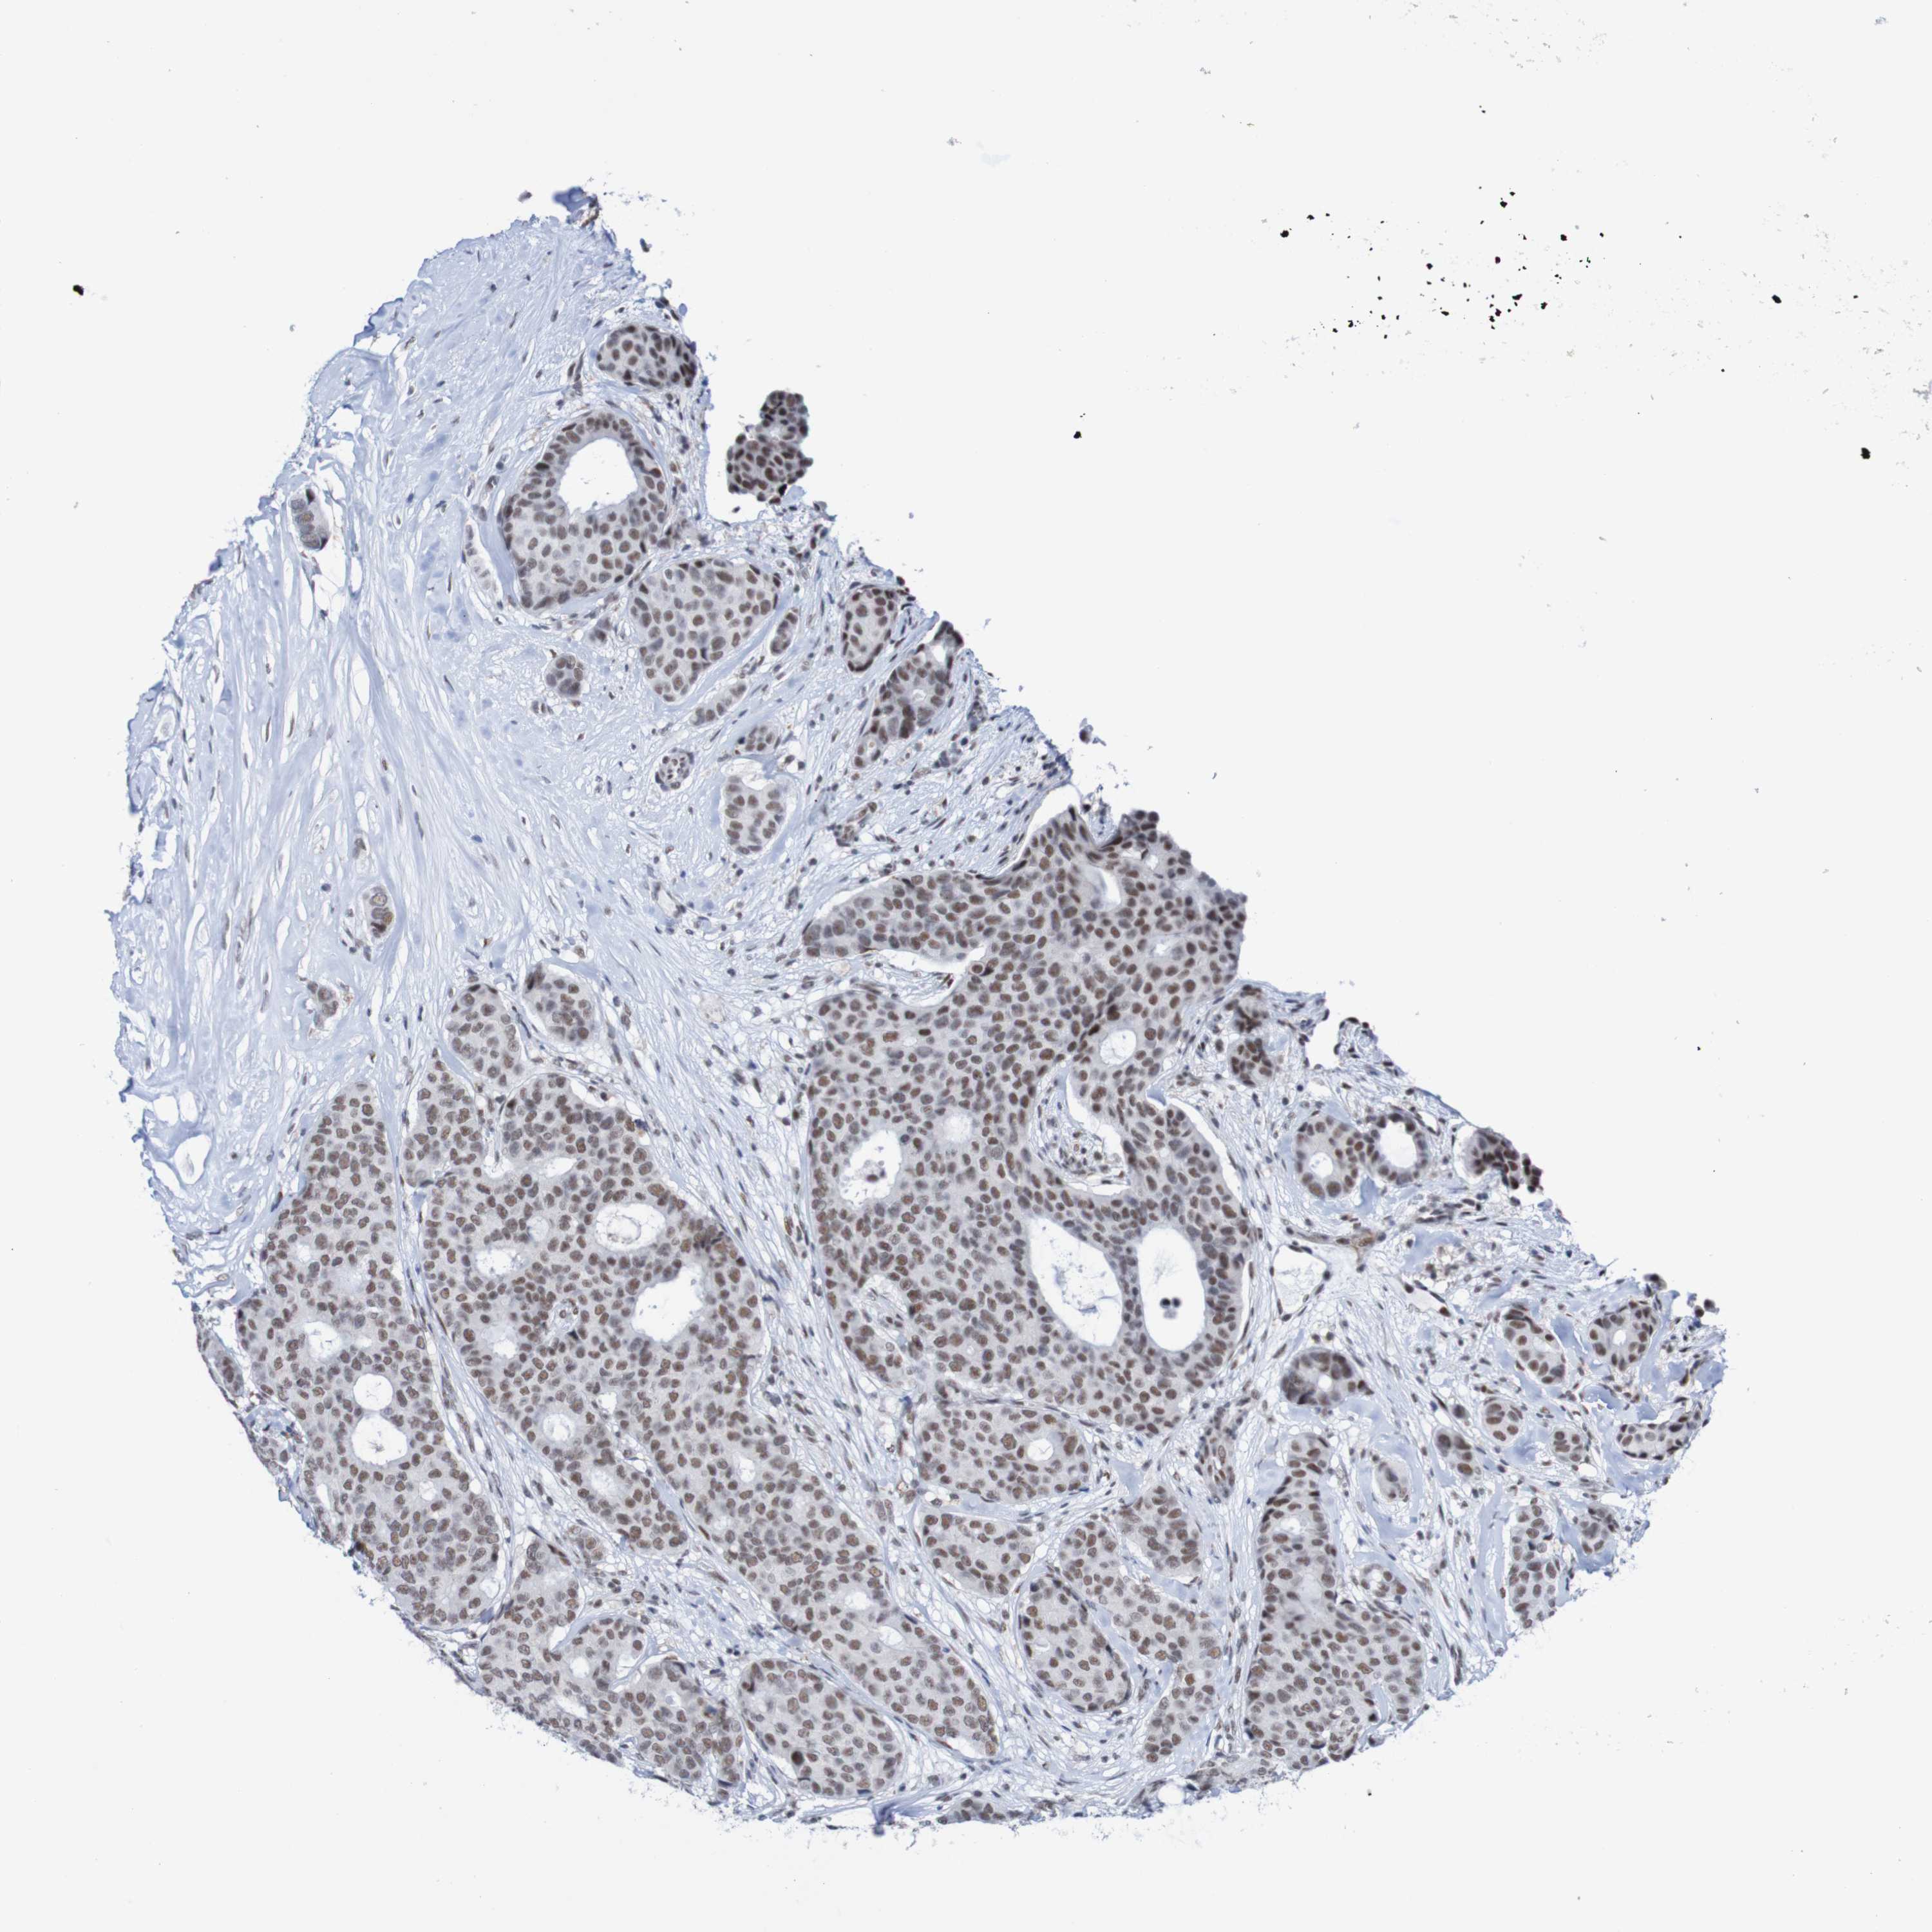

CANCER BREAST CANCER Show tissue menu

BRCA TCGA BRCA VALIDATION PROTEIN EXPRESSION